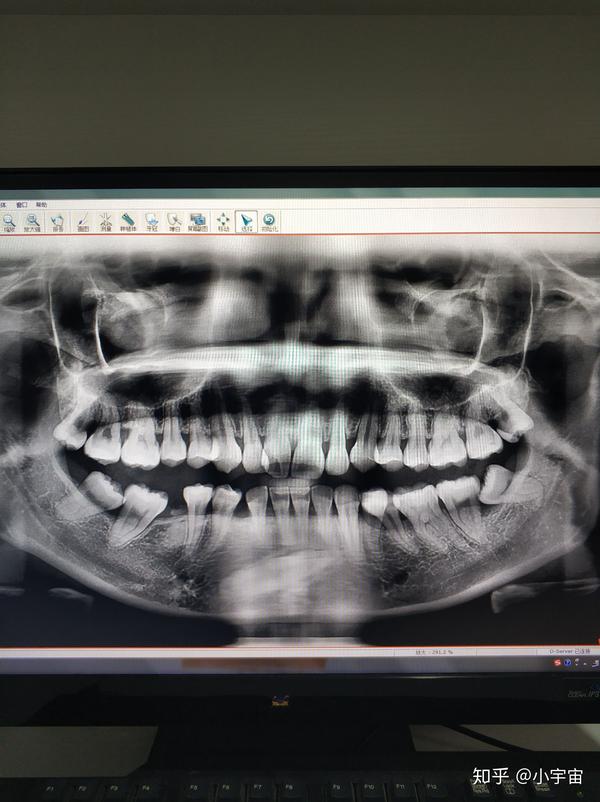

好开始我的正畸之路了,以下是我的牙片

告诉我我是骨性龅牙,牙齿拥挤要拔牙,中度地包天,你先拍牙片定方案吧